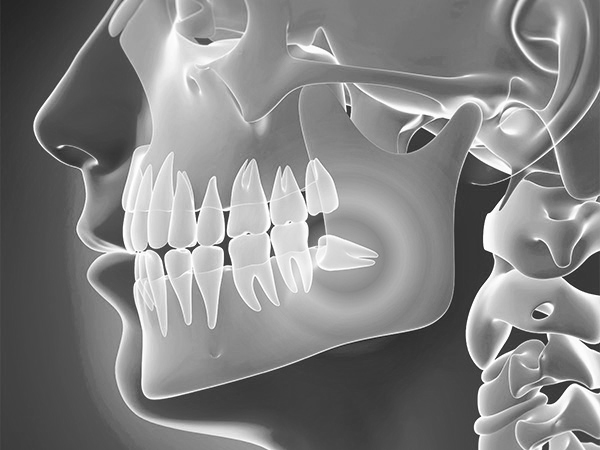

사랑니가 신경과 맞닿아 있는 상황을 제외하고는 안전하고 신속하게 발치가 가능합니다.

사랑니가 비스듬하게 누워있는 경우에는 수술적인 방법을 통해 발치를 해야 하며 신경과 맞닿아 있는 경우에는 사랑니 발치 시 신경손상의 우려가 있음으로 주의하셔야 합니다.

왜 숙련된 의사에게 받아야 할까요?

사랑니 치료의 경우 여러가지 문제가 발생할 수 있습니다.

경우에 따라서 발치의 방법도 바뀌게 되고, 또한 사랑니 주변의 신경, 턱뼈 등을 신경써야 하기 때문에

숙련된 의사에게 받는 것이 중요합니다.